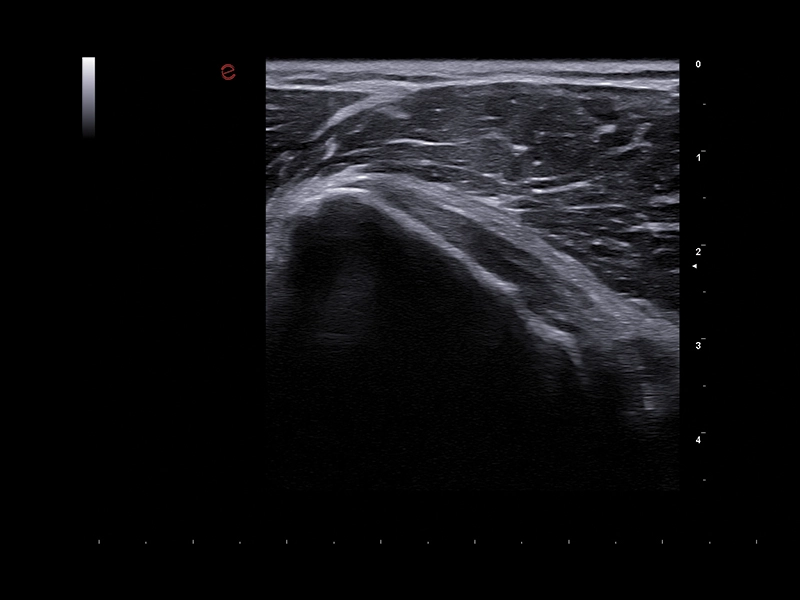

MyLab™Sigma - MSK imaging of the shoulder

MyLab™Sigma - MSK imaging of the shoulder